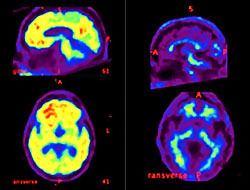

Araştırmacılar, bunamanın en yaygın şekli olan Alzheimer hastalığını belirtiler ortaya çıkmadan birkaç yıl önce belirleyebileceklerine inanıyorlar. Yaklaşımları beynin küçülmesini ve beyni ve omuriliği çevreleyen beyin omurilik sıvısının içindeki "amiloid" isimli proteinin normal seviyesinden az olup olmadığını kontrol edecek.

Uzmanlar, Alzheimer'da beyinde hacim kaybı olduğunu ve omurilik sıvısında daha az amiloid proteini bulunduğunu biliyorlar. Şimdi araştırmacılar, bunlar oluşmadan çok önce bunu belirlemeye çalışıyorlar.

Araştırmacılar, bunu doğrulamak için 105 sağlıklı gönüllüyü bir dizi testten geçirdiler. Katılımcılara, amiloid seviyesini belirlemede beyin omurilik sıvısını kontrol etmek için bel bölgelerinde bir delik açıldı ve aynı zamanda beyinde küçülme olup olmadığını hesaplamak için beyin MR'ı çekildi.

Sonuçlar normal bireylerin düşük miktarda amiloid proteni içeren beyinlerinin (grubun yüzde 38'i) diğer grup kadar hızlı küçüldüğünü ortaya çıkardı. Eğer bu gönüllülerden herhangi birinde Alzheimer görülürse, bilim adamları şüphelerinin doğrulanacağını açıkladılar.